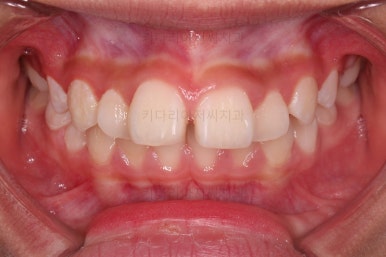

부산소아교정 마무리 사진입니다.

프리올소로 유지과정까지 총 2년 3개월 가량 걸렸고요.

이정도 마무리면 굳이 2차교정까지 안해도 되겠죠?

정교한 조절은 안했지만 치열이나 교합/맞물림 등 매우 좋아졌습니다.